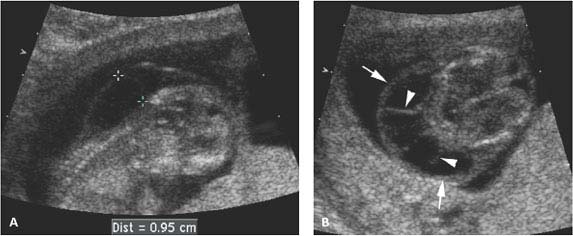

Cystic hygroma is a type of lymphangioma with large dilated cystic lymph spaces which usually occur in the neck. The sonographic findings in eight children with surgically proved cystic hygroma were reviewed and correlated with the pathologic specimens. Six tumors occurred in. Your doctor will order an amniocentesis if they notice a cystic hygroma during an ultrasound.